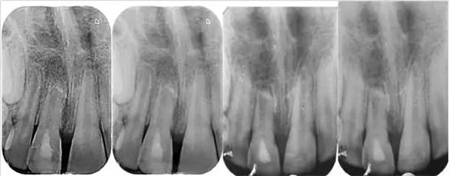

影像學(xué)檢查:根尖片以及全景片(圖2)提示牙槽骨骨折,根尖挫入至唇側(cè)骨板或鼻底。根尖片提示牙11,12 和21根尖發(fā)育不完全,呈喇叭口狀。受累牙的根管壁薄且不完全成形(圖2)。牙片顯示沒有冠折和根折。

( 圖2)